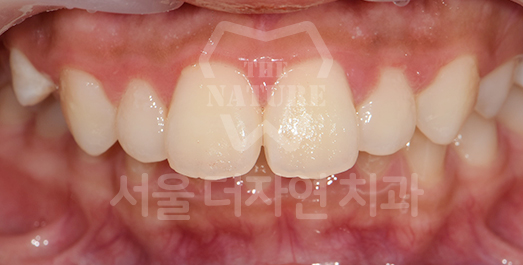

Impacted Tooth Solution

An impacted tooth remaining within the alveolar bone can cause damage to adjacent teeth.

Orthodontic traction is used to guide the impacted tooth into its correct position,

allowing it to erupt and seat normally within the dental arch.

-

AFTER: 2013.07.08

Side effects such as root resorption and gingival recession may occur.